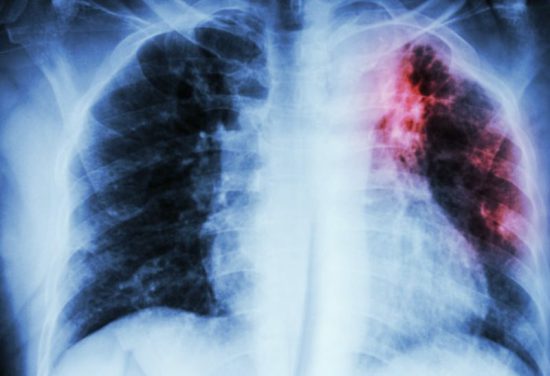

Día Mundial de la Tuberculosis

El 24 de marzo se celebra el Día Mundial de la Tuberculosis para conmemorar el descubrimiento en 1882 de la bacteria responsable de la enfermedad: mycobacterium tuberculosis. Un 24 de marzo de 1882 Robert Koch anunció al mundo este importante descubrimiento.